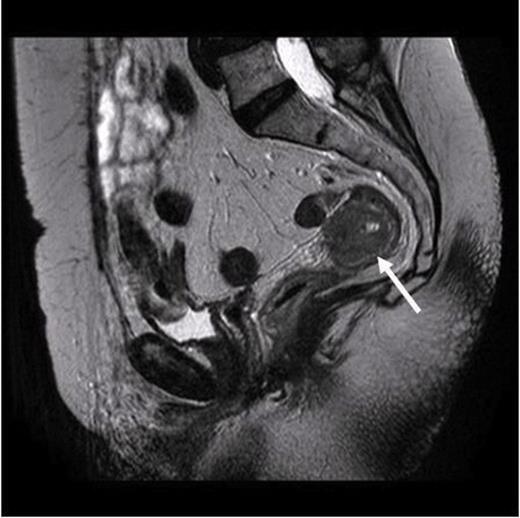

Considering her previous history of invasive breast cancer, pathologist performed immunohistochemistry of the colonic biopsies. The tumour cells were strongly positive for Cytokeratin (CK) 7 with focal positivity for ER but were negative for both Carcino Embryonic Antigen (CEA) and CK 20. The above immunohistochemistry profile with previous history of breast cancer favoured a metastatic breast origin over a primary colonic cancer even though the clinical and colonoscopic findings were not typical. The staging CT scan didn’t show any evidence of metastasis and the MRI scan revealed a locally advanced tumour with involvement of mesorectal facial margins with possible involvement of the peritoneum locally (Figure 3). The bone scan failed to reveal any evidence of active metastatic disease.

MRI scan. Arrow pointing to the localized tumour in the rectum with no evidence of widespread metastasis